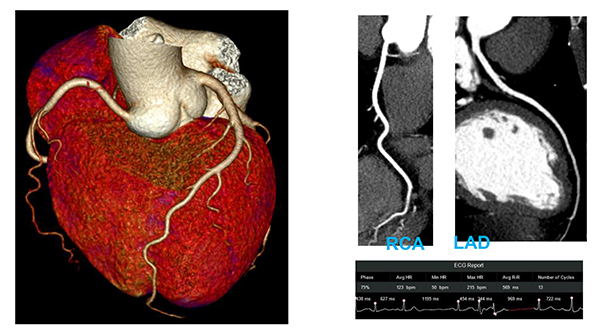

uCT 960+は320列640スライスで16㎝をカバーするCT装置で,外観はボアサイズ82cmと開口径が大きいのが特徴で,よりフレキシブルなポジショニングと容易なアクセスを実現した。また,0.25 sec/rotationの高速SCANが可能で,その高速SCANと16cmのSCAN範囲で一心拍での低線量,高画質での心臓検査を可能とする。

One beat with Free Breathingによる画像(Arrhythmia(50~215 bpm))